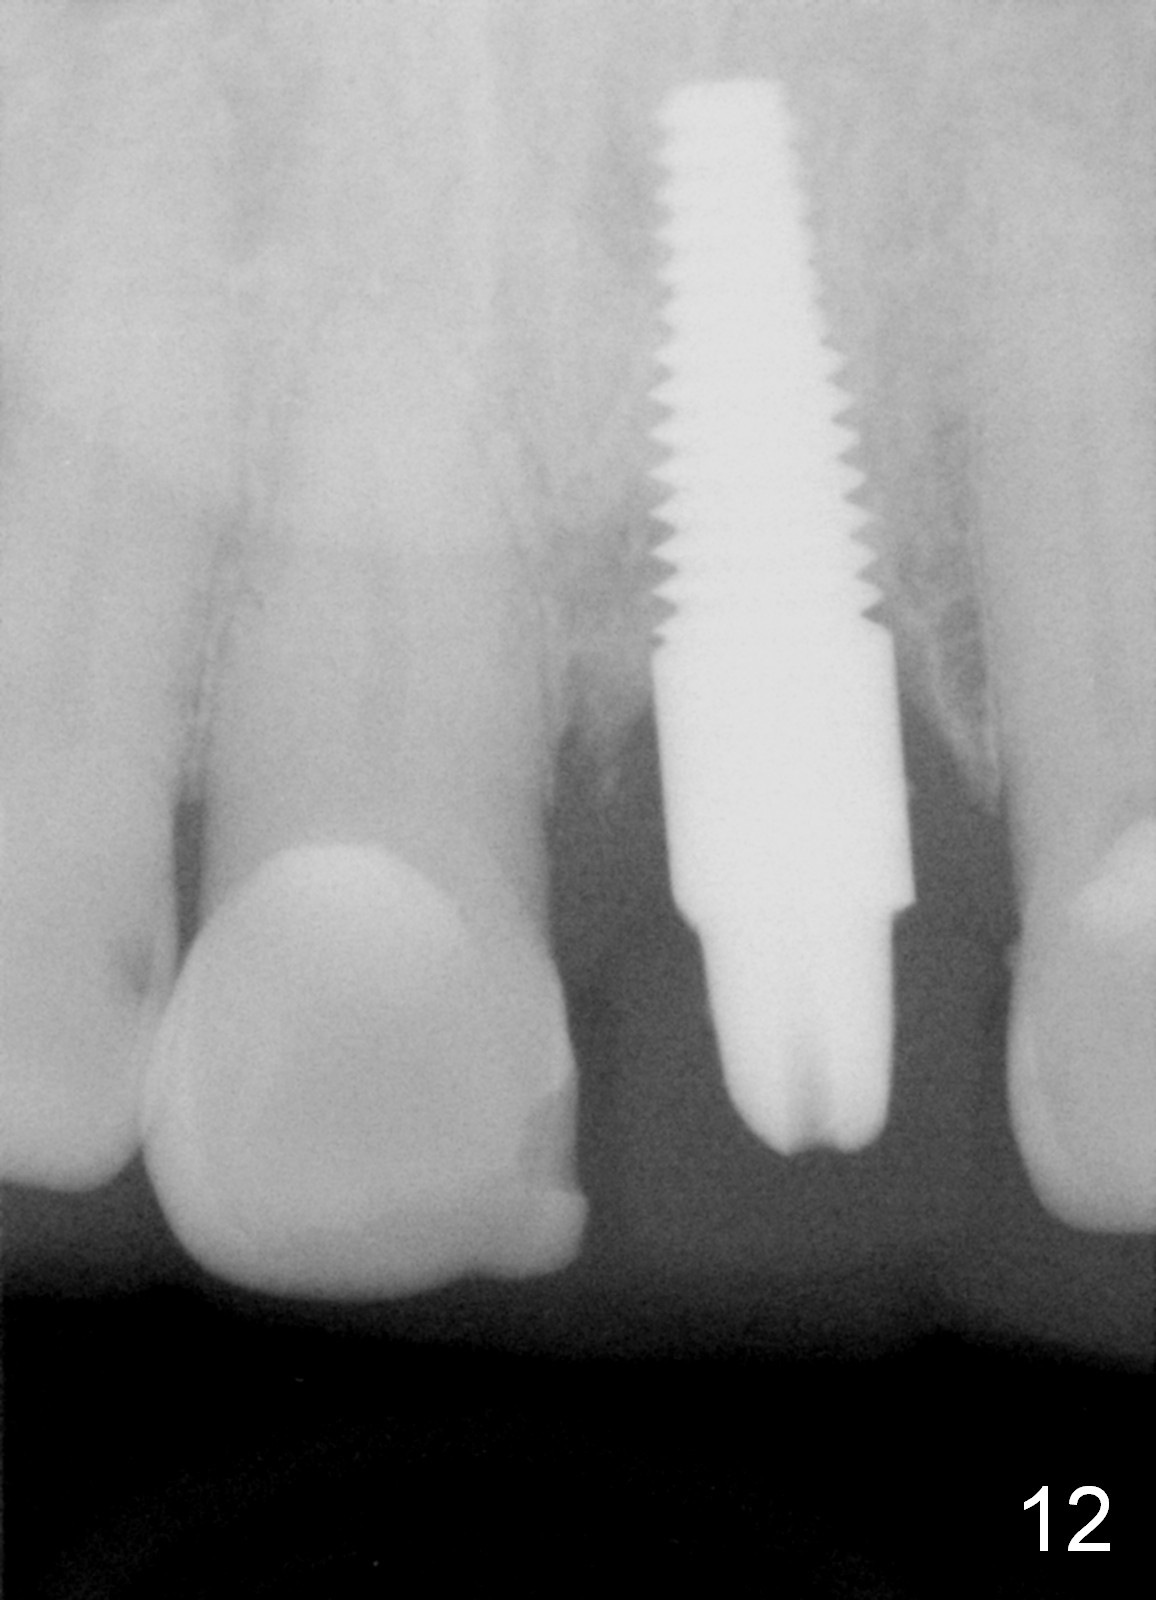

Postop tenderness lasts for two days. The palatal swelling is unnoticeable 7 days postop (Fig.9 *, as compared to A in Fig.8). The bone remains stable around the implant (Fig.10), while the gingiva healthy around the immediate provisional (Fig.11) 5 months postop. Due to insurance limit, the permanent restoration is delayed (16 months postop, Fig.12). The patient is satisfied with the function and appearance 3 years 8 months postop (21 months post cementation, Fig.13,14). PA is taken 4 years 1 month postop (2.5 years post cementation, Fig.15). The lamina dura forms from the most coronal threads (Fig.16). Although there is no bone loss around the implant (Fig.17), metal starts to show 5 years 2 months postop (Fig.18 ^), probably related to the buccal placement, too large the implant for the site or buccal plate atrophy (Fig.19).